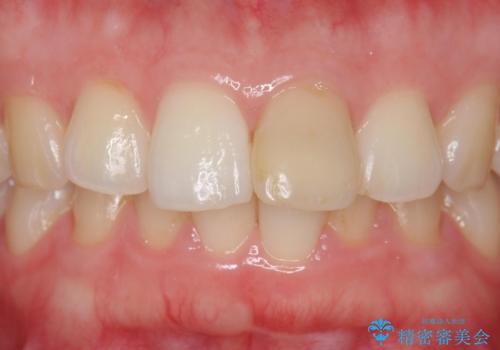

歯ぐきの形を整えることで精度の良い詰め物を入れることができました。